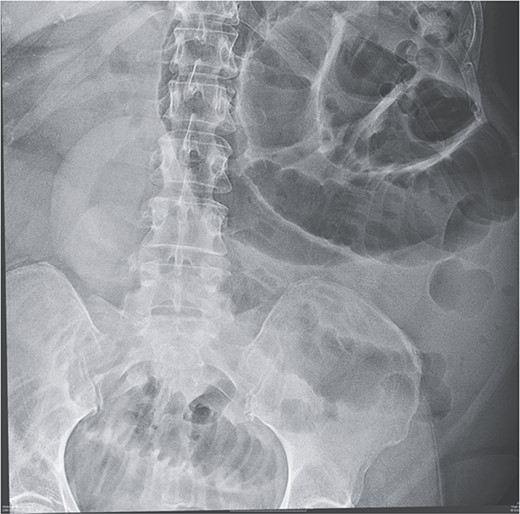

Given her abdominal symptoms and signs, she was subjected to an abdominal X-ray (Fig. 1), which showed multiple distended loops of the small bowel, and a chest X-ray, which showed left basal atelectasis. A working diagnosis of SBO was made. She was put nil by mouth. A nasogastric tube and a urinary catheter were inserted. After initial resuscitation, she was subjected to CTAP with contrast. The findings of the CTAP were in keeping with acute distal SBO secondary to an ileo-ileal intussusception. No obvious mucosal mass was stated in the initial report (Figs 2 and 3).

CT Abdomen: MPR reconstruction of the plane of intussusception showing a distal lipoma and proximal start of intussusception.